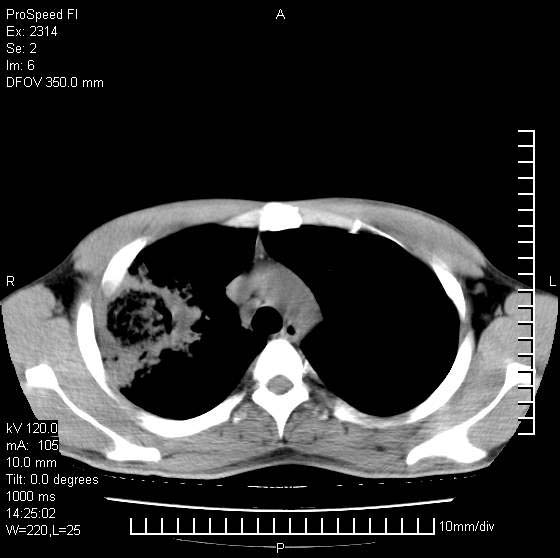

男性,再生障碍性贫血,入院前发热10天,最高40c,右侧胸痛,外院ct示右上,中肺边缘模糊的球性影(就是我现在图中标示的范围),考虑炎症,在我院使用头孢呋辛,洛美沙星10天,高烧消退,自感下午稍有发热,但今天ct示右上,中肺病灶明显扩大,还是考虑炎症,看其中的球型影是否霉菌感染??,是否能排除结核?

右肺中叶外侧段病变,上缘界限不清,下缘锐利,以段性发病为主,内见巨大空洞及空洞内容物,结合病史首先考虑:化脓性肺炎。不除外霉菌感染!

考虑霉菌感染.理由1\\有临床基础疾病,2\\有坏死的空腔,其内可见软组织影.

支持考虑真菌感染,内部密度低些,且与外壁有分离,不符合肺脓肿表现,但最好有前片对比,

片状高密度影内见空洞影,内可见球形软组织密度影,并有新月征,考虑霉菌感染.